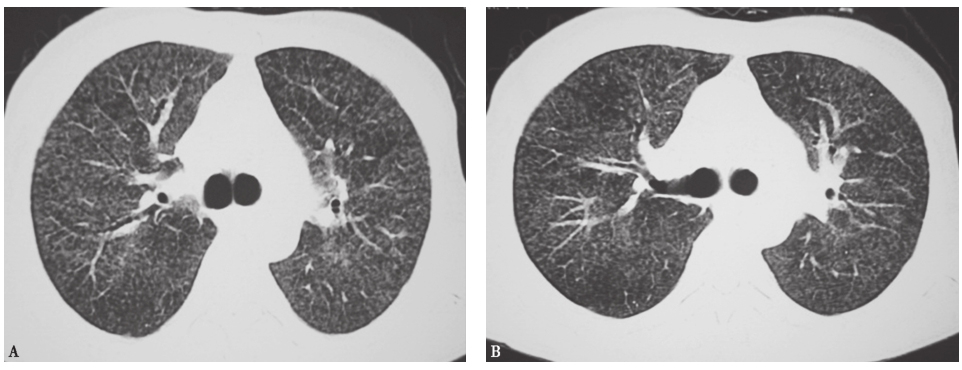

图2血行播散型肺结核胸部CT表现

胸部CT可见两肺弥漫小结节影,大小、分布、密度较均一